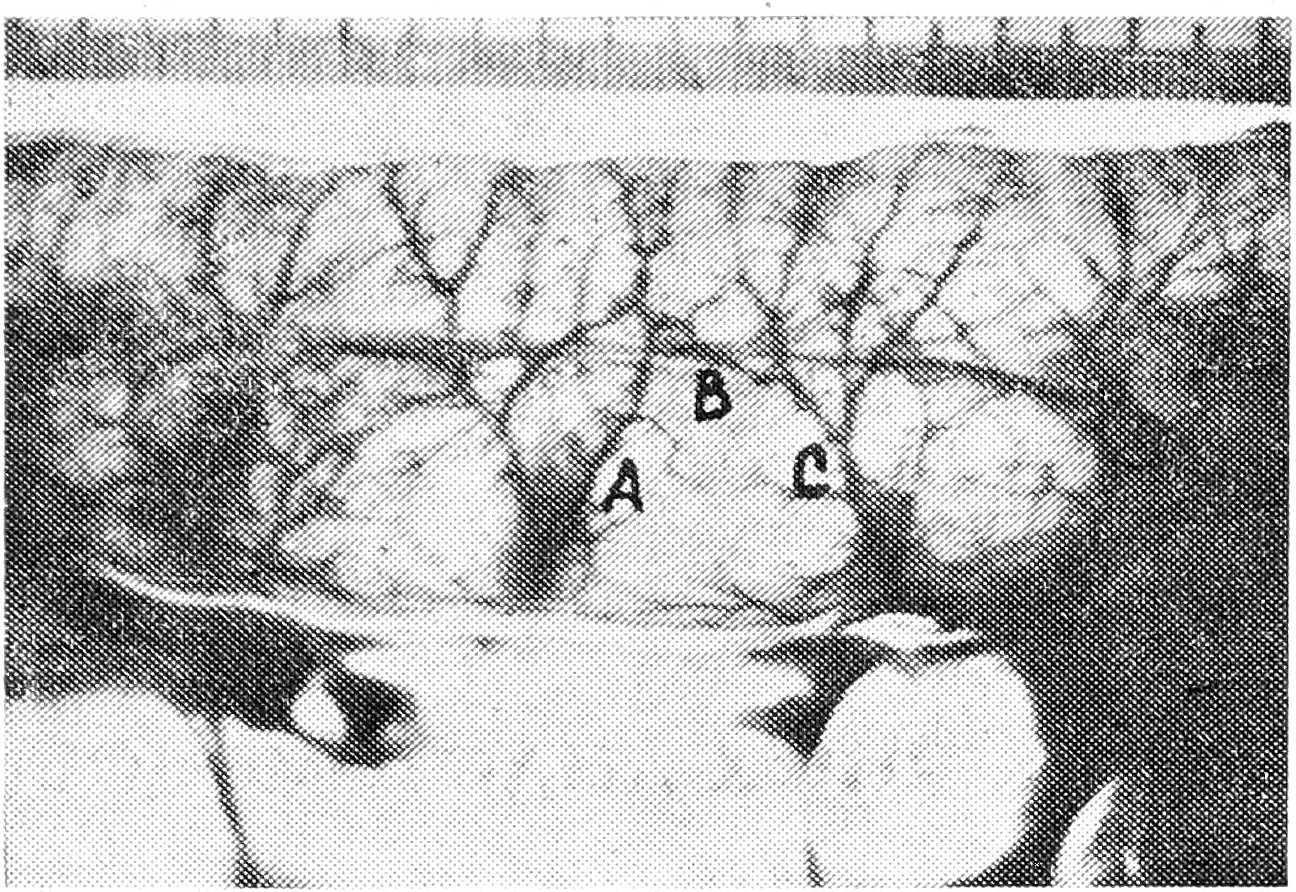

Шовные полосы могут быть связаны с длинным или коротким прямым сосудом. В первом случае брыжеечный отдел кишки оказывается лишенным собственного источника кровообращения: Интрамуральный кровоток обеспечивается за счет ветвей длинных прямых сосудов (рис. 1). Поток крови при этом распространяется от брыжеечного к противобрыжеечному краю и далее по дугообразному анастомозу — ветви, возникшей после дихотомического деления интрамурального отрезка прямого сосуда,—к брыжеечному краю. Короткий же сосуд ветвится в пределах брыжеечного отдела кишки (рис. 2).

Рис. 1. Кровоснабжение шовной полосы длинным прямым сосудом. АВС — основная анастомотическая дуга между сохраненным сосудом А и перевязанным сосудом С.